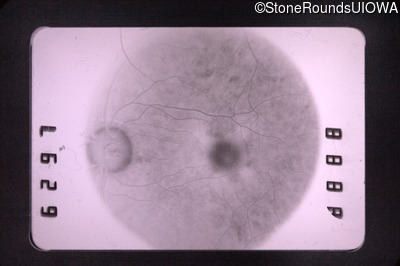

Fluorescein Angiography - Right - 20/50 +1

Exemplar

Fluorescein Angiography - Left - 20/400